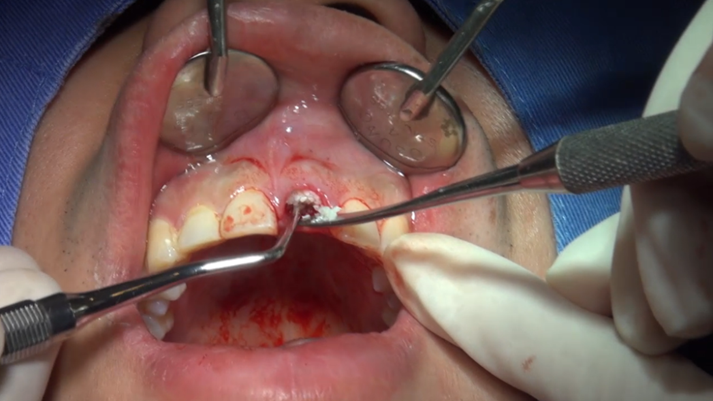

Clinical case: Extraction, immediate placement & loading using

R2GATE solution in aesthetic zone

- Courtesy of Dr. Jong-Cheol Kim, Korea-

Dr. Jong Cheol Kim, immediate loading, digital guided surgery, Digital ONE-DAY Implant, maxillary anterior, #21, guided surgery, immediate loading, AnyRidge, R2GATE, Mega ISQ, MEG Torq, R2GATE Full Surgical Kit

AnyRidge implant system, R2 Guide, R2GATE Full Surgical Kit, Mega ISQ